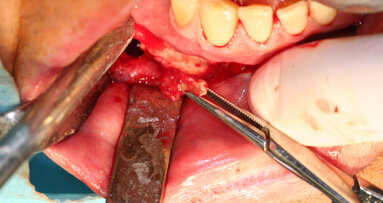

V ortognátní chirurgii využíváme piezochirurgii hlavně k osteotomiím pomocným, základní osteotomie v linii Le Fort I, provedení sagitální osteotomie mandibuly a genioplastiky provádíme rotačními nástroji nebo oscilační pilou – důvod je ale čistě ekonomický při vyšší ceně piezochirurgických koncovek (obr. 3, 4).

Stále častěji jsou na naši kliniku doporučováni pacienti, u nichž došlo k trvalé ztrátě citlivosti oblasti dolního rtu a brady nebo naopak neuralgiformním bolestem nervus alveolaris inferior v důsledku jeho poranění při implantaci nebo chirurgické extrakci retinovaného zubu. V těchto případech provádíme deliberaci tohoto nervu buď z přístupu ze sagitální osteotomie mandibuly nebo pomocí piezochirurgie. Následně odstraníme amputační neurom a nerv mikrochirurgicky rekonstruujeme (obr. 5a, 5b).